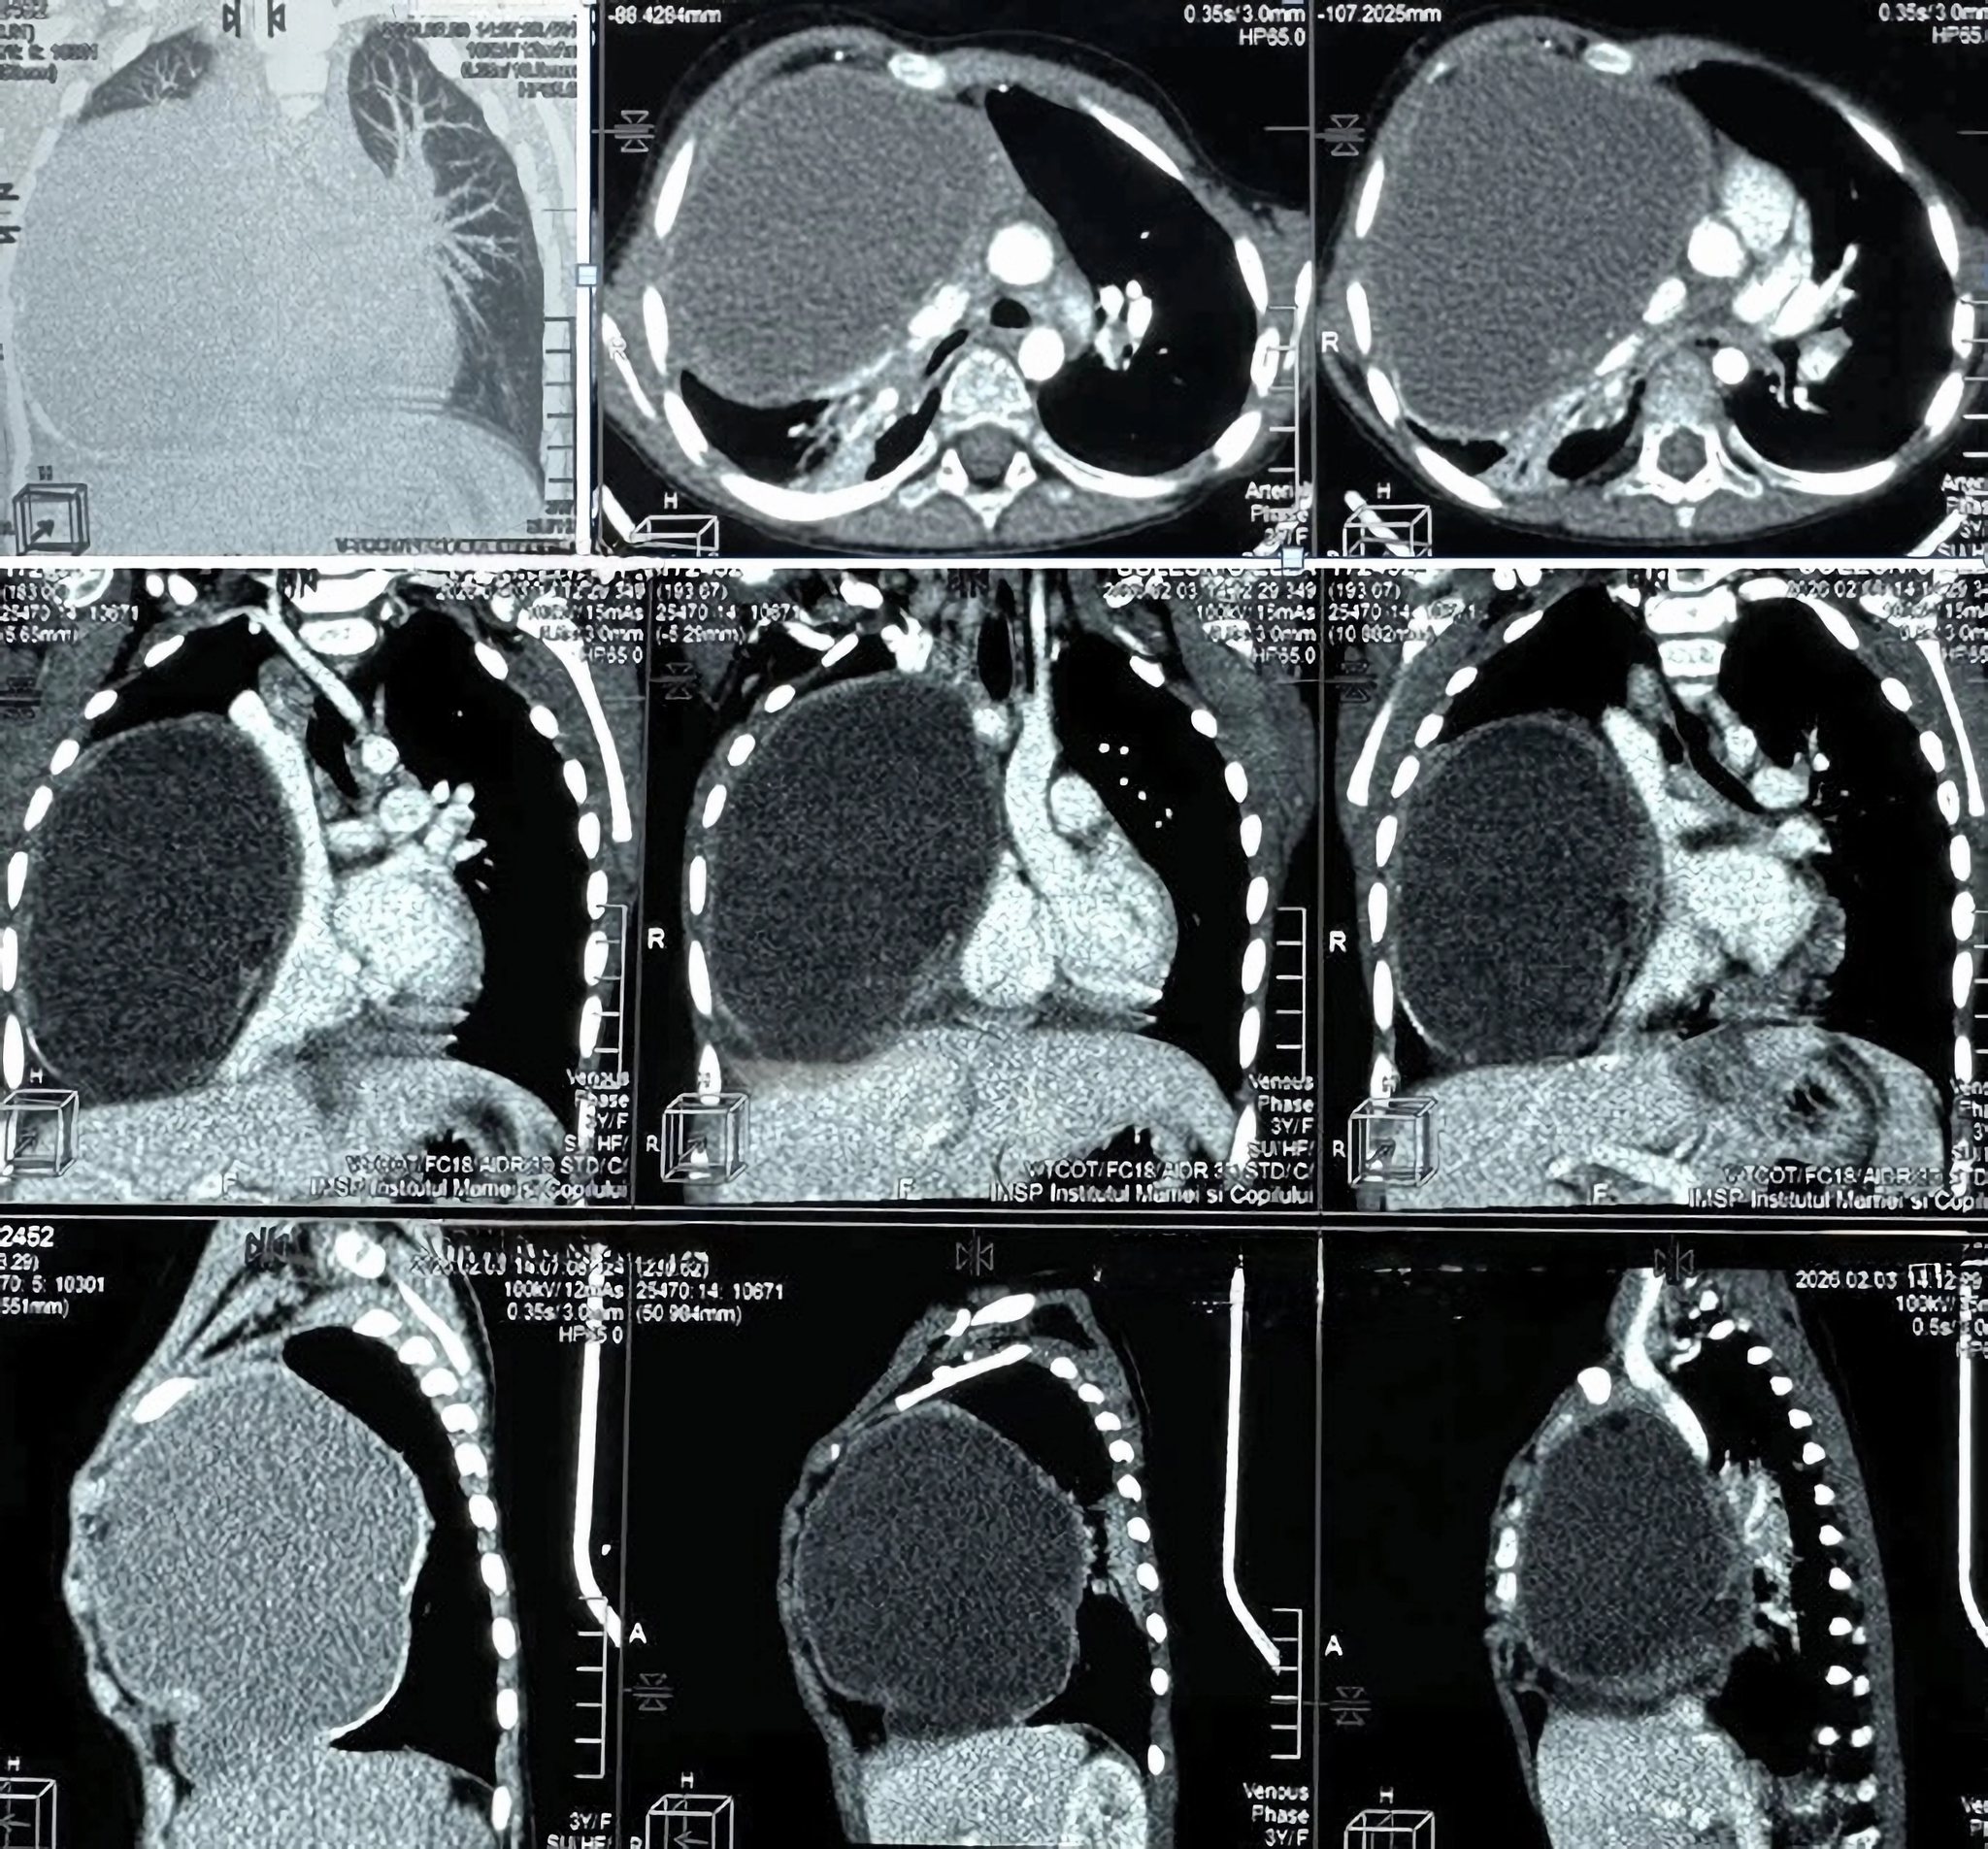

Investigațiile imagistice realizate în cadrul serviciului radiologie și medicină nucleară au scos la iveală o situație extrem de gravă:

- o tumoră masivă (aproximativ 12 x 9 x 10 cm) localizată în hemitoracele drept;

- formațiunea ocupa circa 80% din cavitatea pleurală, comprimând aproape total plămânul drept și exercitând o presiune severă asupra structurilor mediastinale;

- tomografia a sugerat un caracter multicomponențial (posibil teratom), asociat și cu o anomalie vasculară rară (arteră subclavie dreaptă aberantă).